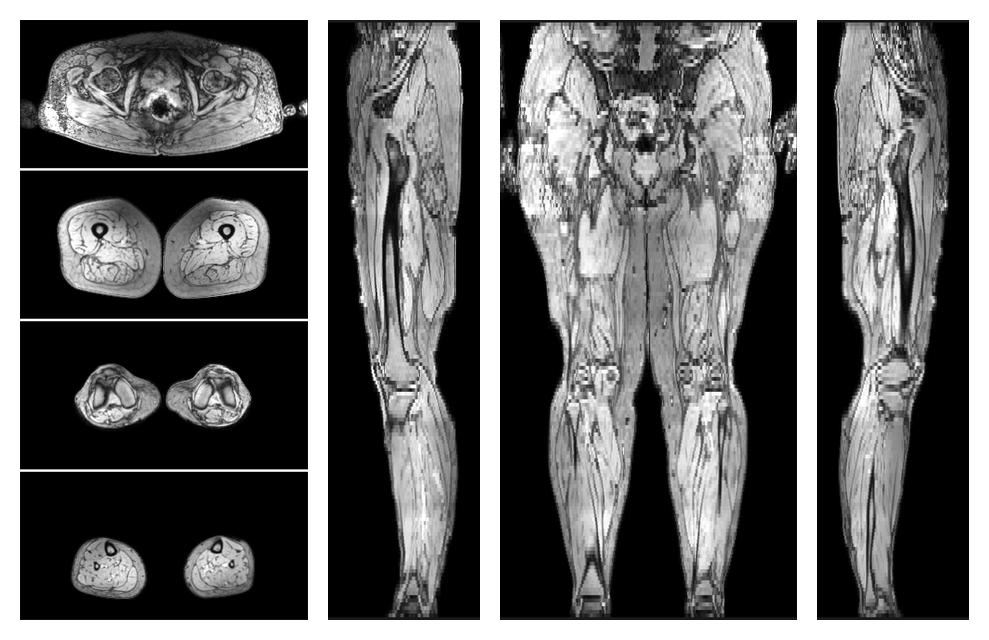

• Out phase image

The out-phase image of the dixon reconstruction for water fat quantification.

• Fat fraction

The fat fraction of the lower extremity obtained from the dixon reconstruction for muscle water fat quantification.